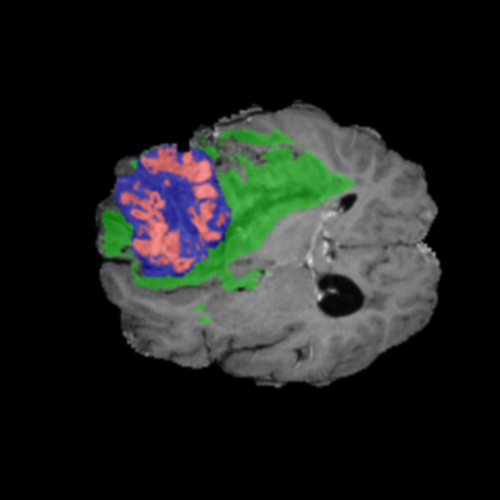

Ejemplos de Modalidades MRI

Visualización de las 4 modalidades de resonancia magnética y las segmentaciones de zonas tumorales utilizadas para entrenar el modelo

Núcleo HGG

Núcleo

Edema HGG

Edema

Realce HGG

Realce

Tumor Completo HGG

Tumor Completo

Núcleo Edema Realce

🎯 Zonas Tumorales Segmentadas

• Núcleo (NCR): Región central no viable y necrótica del tumor

• Edema (ED): Inflamación (acumulación de líquido) en tejido cerebral sano circundante

• Realce (ET): Parte activa y viable del tumor, identificada por captación del contraste en T1ce